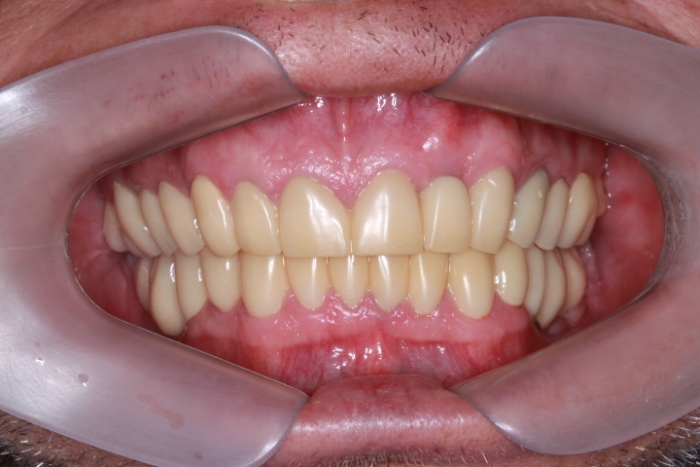

Imagem Próteses Definitivas em Setembro de 2016

Próteses Definitivas e Facetas em Porcelana, em Setembro de 2016

Sorriso Final, em 2016